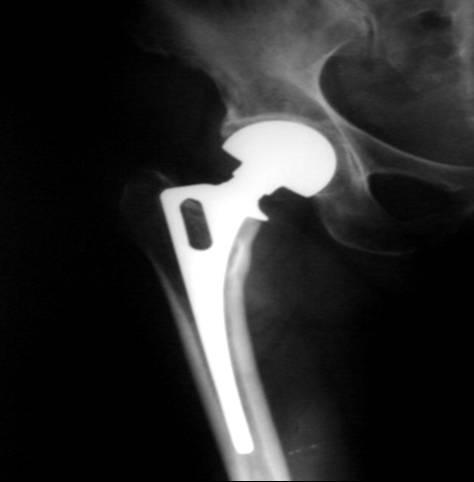

Traumatic arthritis is a type of arthritis resulting after few years of a hip fracture that has been treated. It requires removal of nail, pin etc and introduction of a new artificial hip joint THR

X-rays are used to determine the extent of degeneration to the cartilage or bone and may suggest a cause for the degeneration of the hip joint.